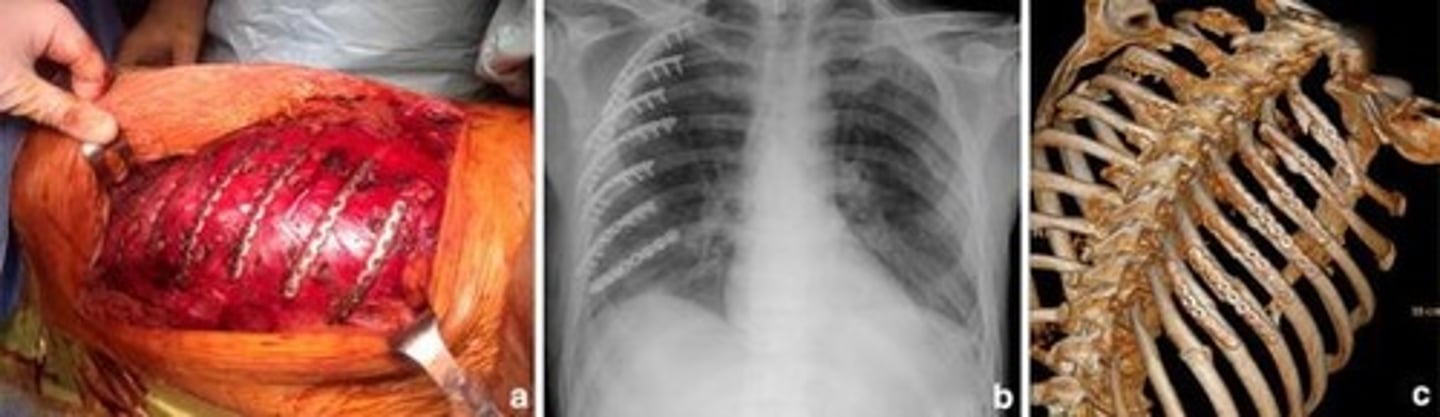

What defines flail chest?

Multiple rib fractures at two or more sites leading to chest wall instability and respiratory distress.

What is the treatment approach for flail chest?

Supportive care, possible ventilation, and surgery for severe cases.